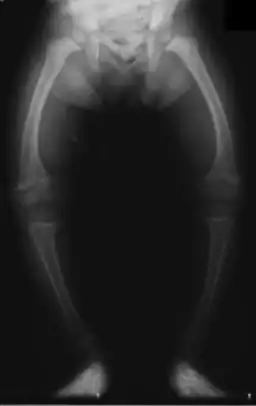

Primidone, along with phenytoin and phenobarbital, is one of the anticonvulsants most heavily associated with bone diseases such as osteoporosis, osteopenia (which can precede osteoporosis), osteomalacia, and fractures.[31][32][33] The populations usually said to be most at risk are institutionalized people, postmenopausal women, older men, people taking more than one anticonvulsant, and children, who are also at risk of rickets.[31] Bone demineralization is suggested to be most pronounced in young people (25–44 years of age),[32] and one 1987 study of institutionalized people found that the rate of osteomalacia in the ones taking anticonvulsants—one out of 19 individuals taking an anticonvulsant (vs. none among the 37 people taking none) —was similar to that expected in elderly people. The authors speculated that this was due to improvements in diet, sun exposure, and exercise in response to earlier findings, and/or that this was because it was sunnier in London than in the Northern European countries, which had earlier reported this effect.[33] In any case, the use of more than one anticonvulsant has been associated with an increased prevalence of bone disease in institutionalized epilepsy patients versus institutionalized people who did not have epilepsy. Likewise, postmenopausal women taking anticonvulsants have a greater risk of fracture than their drug-naive counterparts.[31]

Anticonvulsants affect the bones in many ways. They cause hypophosphatemia, hypocalcemia, low vitamin D levels, and increased parathyroid hormone. Anticonvulsants also contribute to the increased rate of fractures by causing somnolence, ataxia, and tremor, which would cause gait disturbance, further increasing the risk of fractures on top of the increase due to seizures and the restrictions on activity placed on epileptic people. Increased fracture rate has also been reported for carbamazepine, valproate, and clonazepam. The risk of fractures is higher for people taking enzyme-inducing anticonvulsants than for people taking enzyme-non-inducing anticonvulsants.[32] In addition to all of the above, primidone can cause arthralgia.[24]